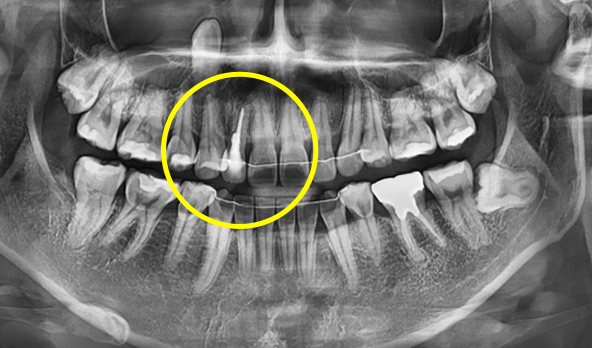

수술 전, 이미 치료는 시작됩니다

CT 정밀 분석 & 3차원 시뮬레이션

수술 당일을 위한 모든 준비를 수술 전에 미리 끝내는 단계입니다.

• CT 촬영을 통한 잇몸뼈·신경 위치 정밀 분석

CT 촬영을 통한

잇몸뼈·신경 위치 정밀 분석

• 3차원 분석을 통한 임플란트 식립 위치·각도·깊이 설정

3차원 분석을 통한

임플란트 식립 위치·각도·깊이 설정

• 개인별 수술용 가이드 제작

개인별 수술용 가이드 제작

• 임플란트 기둥 및 보철물 사전 제작

임플란트 기둥 및 보철물 사전 제작

치료 전

발치 후 수술용 가이드를 이용해 정해진 위치에 정확하게 식립 후 미리 만들어 둔 기둥 연결

발치 후 수술용 가이드를 이용해

정해진 위치에 정확하게 식립 후

미리 만들어 둔 기둥 연결